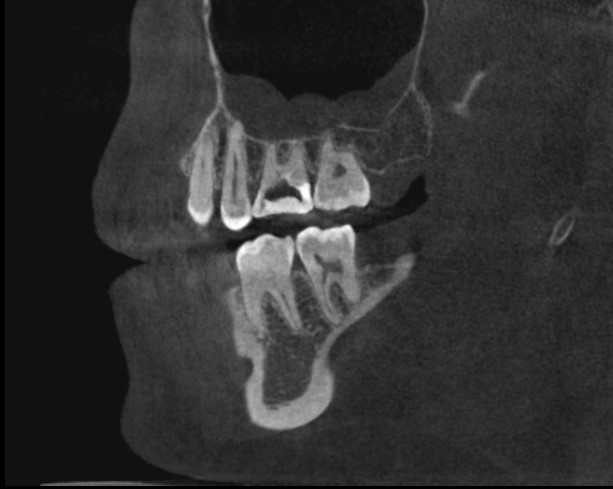

Рис.2 После удаления зубов, выявлена киста синуса

После удаления зубов воспаление в пазухе значительно уменьшилось, на контрольной томограмме выявился четкий контур кисты (рис.